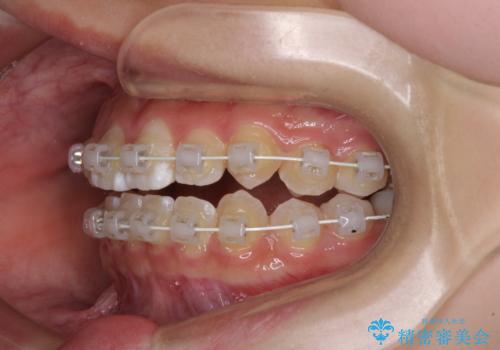

- 前歯のデコボコと磨きにくい奥歯を気にして来院された患者様です。

左右ともに上顎第二大臼歯が外側に転位しており、大変磨きにくくなっているため、補助装置により内側に引き込むことで改善することとしました。

外側を向いていた奥歯は比較的早い時期に歯列に収まり、咬み合わせも磨きやすさも改善することができました。

歯列は元々悪くなかったので、1年ほどで治療を終えることができました。